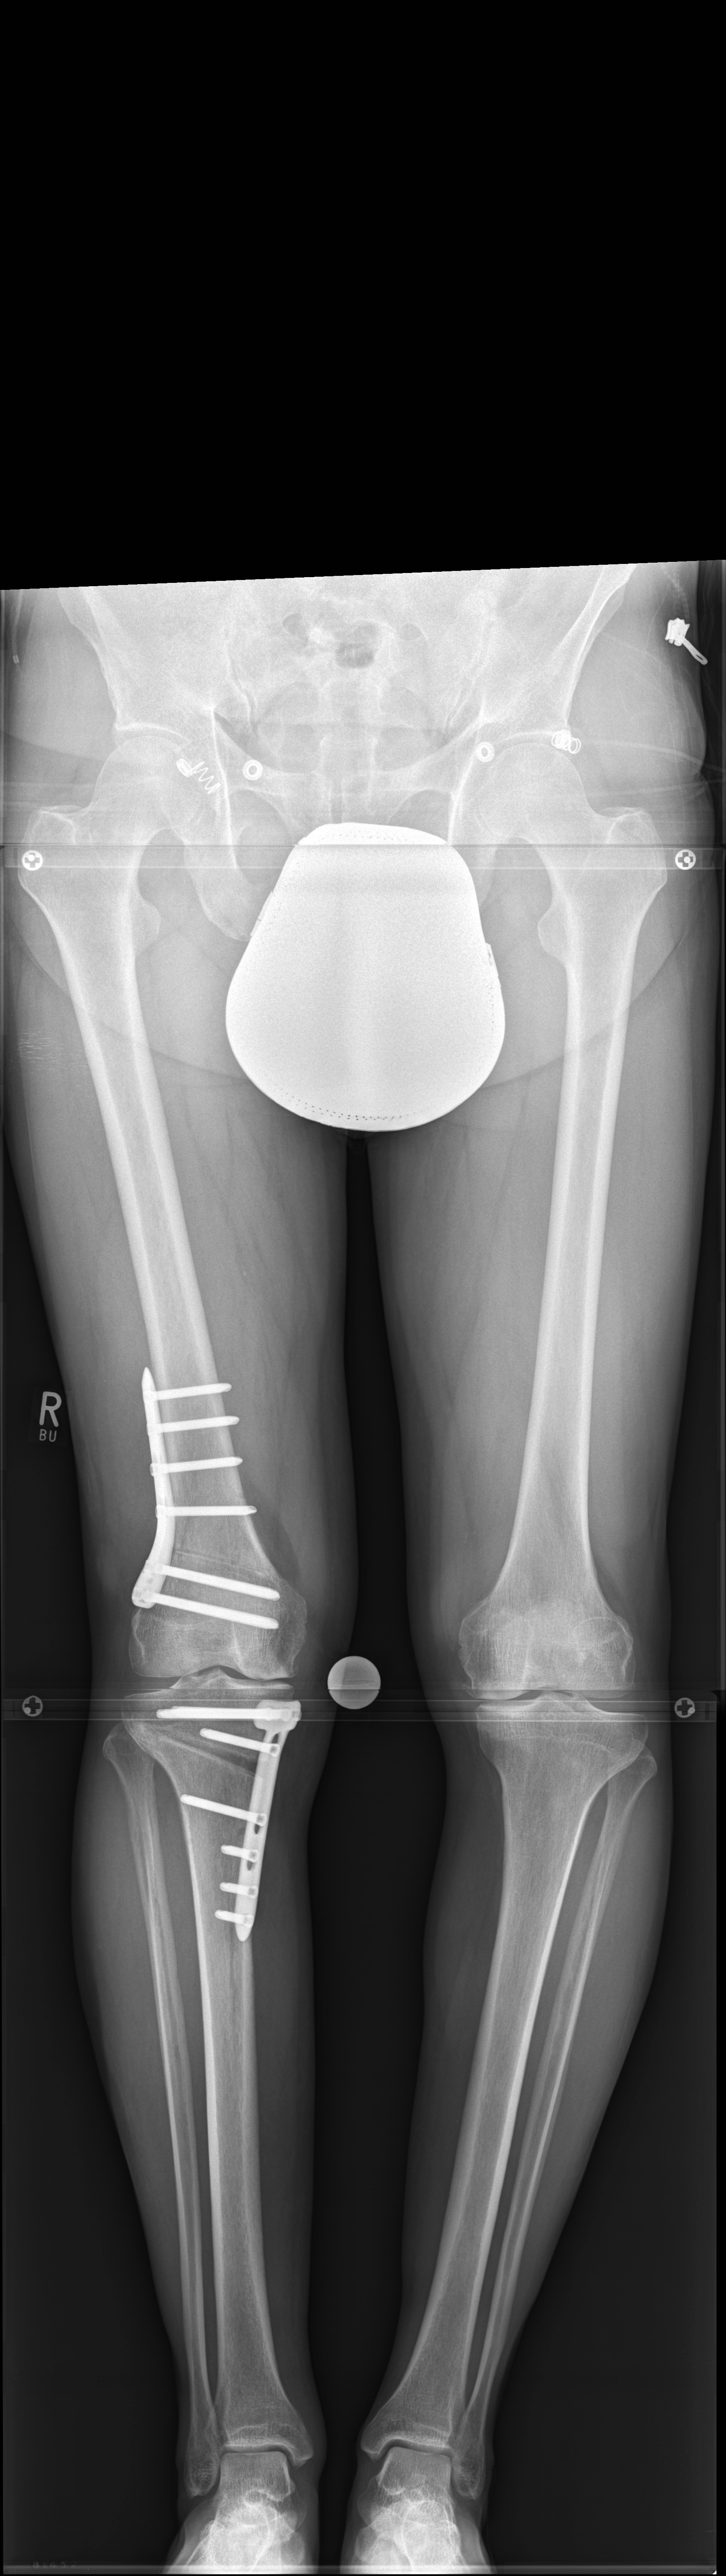

A 52-year-old man, a heavy worker was still able to work, however he was administered pain killers. During weekends only brief bike rides were tolerable. He reported an effusion and on that evening further daily activities were not possible. He complained of pain in the medial compartment. Excessive bowing legs were noticeable. Ligaments were stable in the sagittal plane but there was a medial instability in the coronal plane because of damage to the cartilage. He underwent double-level osteotomy for correction of the leg alignment.

Showcasing a double-level osteotomy case